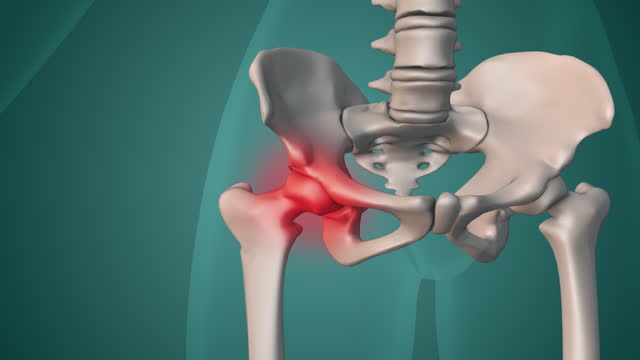

골반 통증 원인 - 골반 바깥쪽

골반 바깥쪽 위쪽 부위가 아프면 대퇴근막장 또는 골반 주변 근육의 문제일 가능성이 높습니다. 골반이 전망으로 비틀릴 때 대퇴근막장이 긴장하며 엉덩이 바깥 부분이 뻐근하게 아프게 됩니다. 고관절을 오래 굴곡시키는 자세나 앉는 자세를 피하고, 관련 근육의 스트레칭을 통해 개선할 수 있습니다.

골반 통증 원인 - 관절

골반 관절의 이상은 골반통증을 일으킬 수 있는 원인 중 하나입니다. 골반 관절의 이상은 관절의 염증이나 변형, 골절 등으로 인해 발생할 수 있습니다. 특히 장시간 동안 한 자세를 유지하거나 골반을 과도하게 사용하는 운동이 해당 관절에 부하를 주어 문제가 생길 수 있습니다.